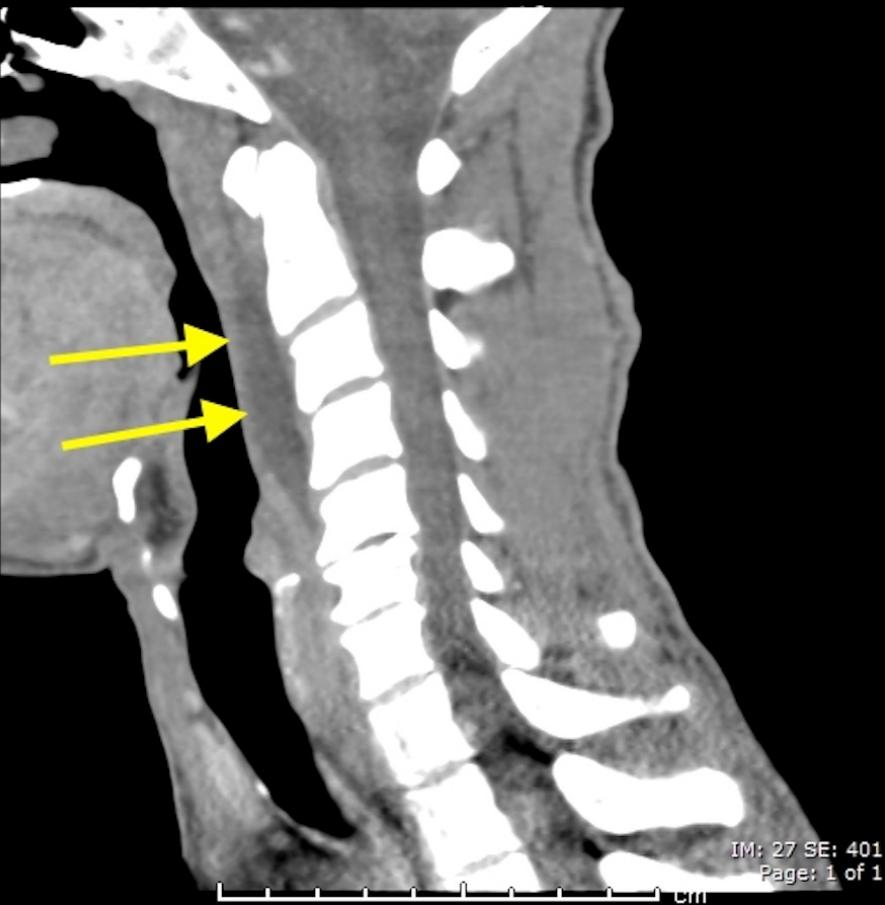

明确诊断主要通过影像学方法,颈椎CT是关键。颈长肌钙化性肌腱炎特异性的影像表现是C1-4椎体前缘软组织肿胀和积液与C1椎体前弓下方不规则钙化沉着共存。

图:C1椎体前弓下方不规则钙化沉着

图:椎前积液

图:椎前积液和C1椎体前弓下方不规则钙化沉着

图:椎前软组织肿胀

颈椎侧位片能够显示上颈椎前纵韧带和颈长肌组成的软组织影增宽,密度增高,正常时宽度为3-4mm,急性炎性水肿时可增宽到1cm以上,并可显示椎前软组织内的钙化影,一般位于C1-2水平。此外,还可见颈肌痉挛引起的颈椎前凸消失。颈椎侧位平片所见的发育性寰椎前弓的下方附属小骨片、寰椎前弓的撕脱骨折以及茎突舌骨肌韧带的钙化极易与本病所见的钙化混淆。

CT的高分辨率能够明确肌腱内的钙化,能够明确是钙化而不是其他骨骼来源的高密度影。钙化一般位于寰椎前弓的下方和枢椎齿状突的前方,少部分可位于下颈椎前侧。CT有助于明确椎体前积液的存在和排除其他病理表现,如骨折或脓肿。MRI对诊断不是必须,但有时可帮助确定软组织异常,排除咽后脓肿,脊椎炎或肿瘤。MRI检查T2加权在椎前可见局限性的裂隙样区域,大多位于C1-4水平,呈高信号改变,这反应是由于炎症引起的积液。T2加权、脂肪抑制序列和T1加权对鉴别积液和脂肪组织、含脂肪的骨髓以及咽后感染、脊椎炎有重要作用。MRI检查在钙化检查方面存在不足,T2加权呈低信号。

40岁男性,低热伴急性颈痛、张口困难1天,颈椎CT提示椎前钙化(箭头),经洛索洛芬60mg,每日三次,连续五天治疗,3天后症状改善,3月复查CT钙化消失。(PMID: 25918175)